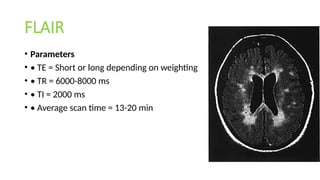

FLAIR

• Parameters

• • TE = Short or long depending on weighting

• • TR = 6000-8000 ms

• • TI = 2000 ms

• • Average scan time = 13-20 min

Coronal angulated slice of a T2

weighted, This MR image of the brain

shows white white matter and grey

matter of the cortex, brainstem, pons,

lateral ventricles and mastoid.

Brain MRI Coronal FLAIR